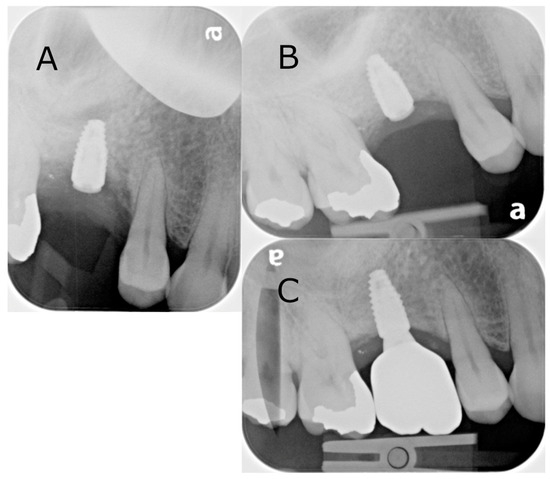

2.1. Case 1: Lateral Sinus Lift

A 64-year-old male patient presented with a complaint of a missing upper right first molar that had been extracted 12 months prior. A CBCT was taken, and restoration with an implant was recommended with lateral sinus augmentation due to the available bone being 3.2 mm in depth (Figure 3A). A surgical treatment plan was formulated, which included a surgical guide to aid in the outline of the bony window and simultaneous implant placement. Consent was obtained from the patient prior to the commencement of the procedure. Local anaesthesia with 4% articaine containing 1:100,000 adrenaline was administered at the buccal and palatal regions of the surgical area. A full thickness flap elevation was performed. The surgical guide was used to direct the lateral window preparation of the sinus wall (Figure 3B,C). The surgical guide sat flush to the cortical plate and dentition. The opening was first outlined and then widened with the piezoelectric diamond burs and round burs from the Lateral Window Bur Kit (Acteon, Lyon, France). Linear osteotomy cuts were performed with rotatory instruments and piezoelectric devices. The resulting window of the sinus wall was reflected superiorly with the mucosa elevated. Simultaneous implant placement and grafting were then performed due to the presence of a satisfactory amount of residual bone. A single Ø 4.1 mm × 10 mm bone level Roxolid SLActive implant (Straumann, Basel, Switzerland) was placed in the preplanned osteotomy site, with Bio-Oss granules and a Bio-Gide membrane (Geislitch, Wolhusen, Switzerland) placed in the sinus cavity (Figure 3D). The full thickness flap was re-approximated with PROLENE suture 5-0 (Ethicon, Raritan, NJ, USA) placed. Typically, three months are required for osseointegration prior to rehabilitation with an implant-supported prothesis, while this may be increased to six months when lateral sinus augmentation is performed at the same appointment. In this case, the surgical site was reviewed six months post-operatively, confirming successful osseointegration and the absence of complications (Figure 4B). The crown was placed at a separate appointment, two months later (Figure 4C).

Figure 3. The use of the surgical guide in a lateral sinus lift: (A) CBCT sagittal cross-section of available bone over crest of ridge; (B) the surgical guide being used to direct the window for the lateral sinus lift; (C) the window for the lateral sinus lift; (D) placement of Bio-Oss granule prior to the membrane placement.

Figure 4. Intraoral radiographs of the surgical site from the lateral sinus lift with simultaneous implant placement: (A) immediately post-operatively following the implant placement; (B) six-month follow-up; (C) crown placement. Note that the letter “a” is pre-printed on the phosphor storage plate upon acquisition, serving as a reference for orientation.